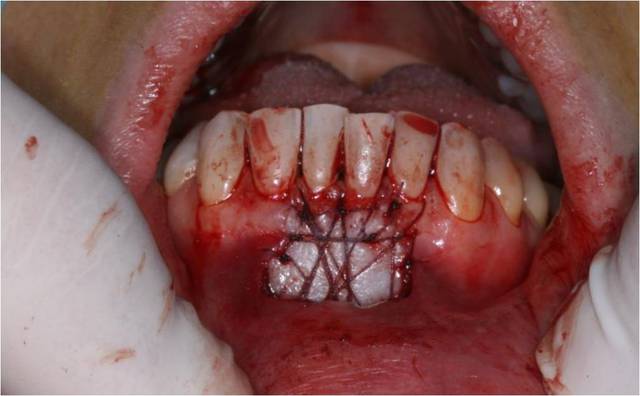

Bon bein voil c'est fait .

Préparer le lit reveveur ok

Le prelevement et la préparation du greffon c'est le plus facile

La ou j'ai eu le plus de difficulté c'est au moment de la mise en place du greffon. Meme en y mettant tout mon courage et ma volonté et du fils 5/0 j'ai pas reussi a suture le lambeau aux papilles . Conclusion il est descendu ... Sinon la freinectomie a pu etre fait sans probleme, lambeau bien plaqué et immobile .

Pour la cicatrisation je croise les doigts.

J'anticipe un peu vos questions :

Pourquoi 2 types de fils ?

j'utilise le 4/0 vicil pour les points facile a mettre en place (aiguille plus grosse et sutures faciles) . Le 5/0 avec sa petite aiguille pour le points plaqué car je n'ai pas le choix .

D'ailleurs le 5/0 prolene c'est vraiment de la merde... il a une memoire de forme et reste embobiné.

Pourquoi ne pas recouvrir toute la racine?

Impossible de suturer au papilles malgres tout mes efforts :/ . La greffe est legerement descendu

Loin de penser que tout soit nikel j'attend vos critiques constructive, surtout celle d'olivier et ceramik :) .

La 2ieme photos correspond au dessin final du lambeau